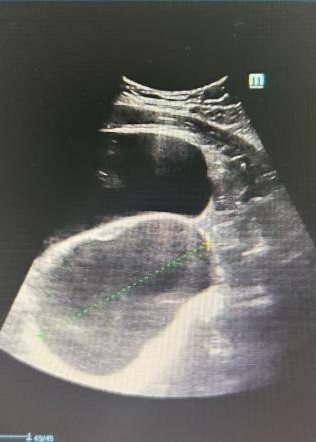

手术顺利开展。术中,任医生在患者右侧卵巢发现一枚约10cm×10cm×9cm的囊实性肿瘤(术后病理确诊为成熟性畸胎瘤),为最大限度保护卵巢功能,团队全程采用钝性分离手法,避免使用电凝器械,每一步操作都精准而轻柔。凭借娴熟的腹腔镜技术,手术过程顺利,出血极少,圆满实现了“微创治疗”与“功能保护”的双重目标。

手术过程